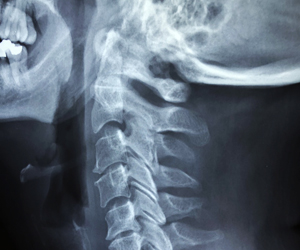

The Center for Neurotechnology is improving health and function by engineering neural devices. We are a collaboration of @UW @MIT @SDSU and the @NSF